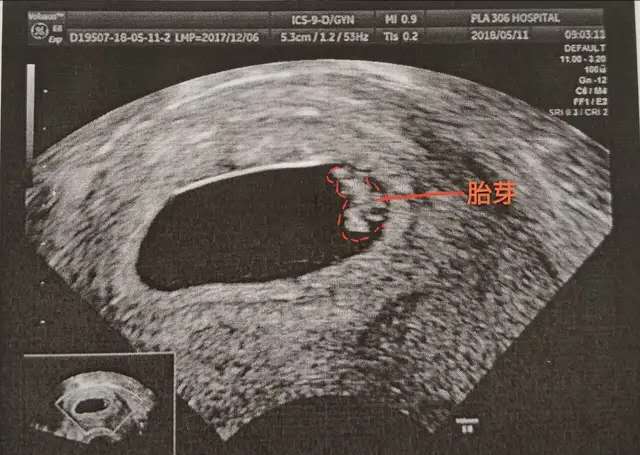

第二部曲胚芽 胚芽就是种子发芽了,一般在孕7周出现,代表着宝宝的进一步发育,这个胚芽随着孕周的增加会慢慢长大,而且也是一个评估胎儿孕周的重要指标,孕周=CRL(cm)+6.5。